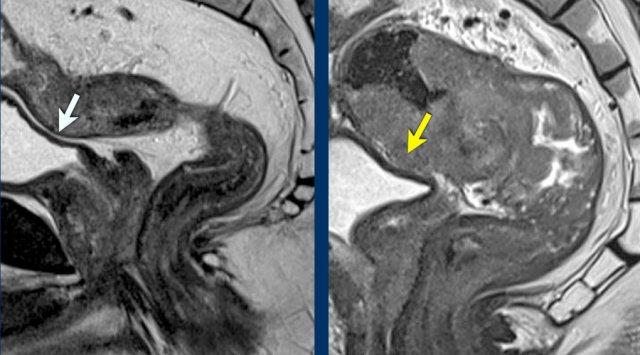

Khối u T4b

Ví dụ về Bệnh cT4b

- Trái: Khối u xâm lấn tuyến tiền liệt

- Phải: Khối u xâm lấn cơ mu trực tràng trái

Ghi chú

Xâm lấn các cơ vân (ví dụ: cơ thắt hậu môn ngoài, cơ mu-trực tràng, cơ nâng hậu môn) được phân loại là bệnh cT4b.